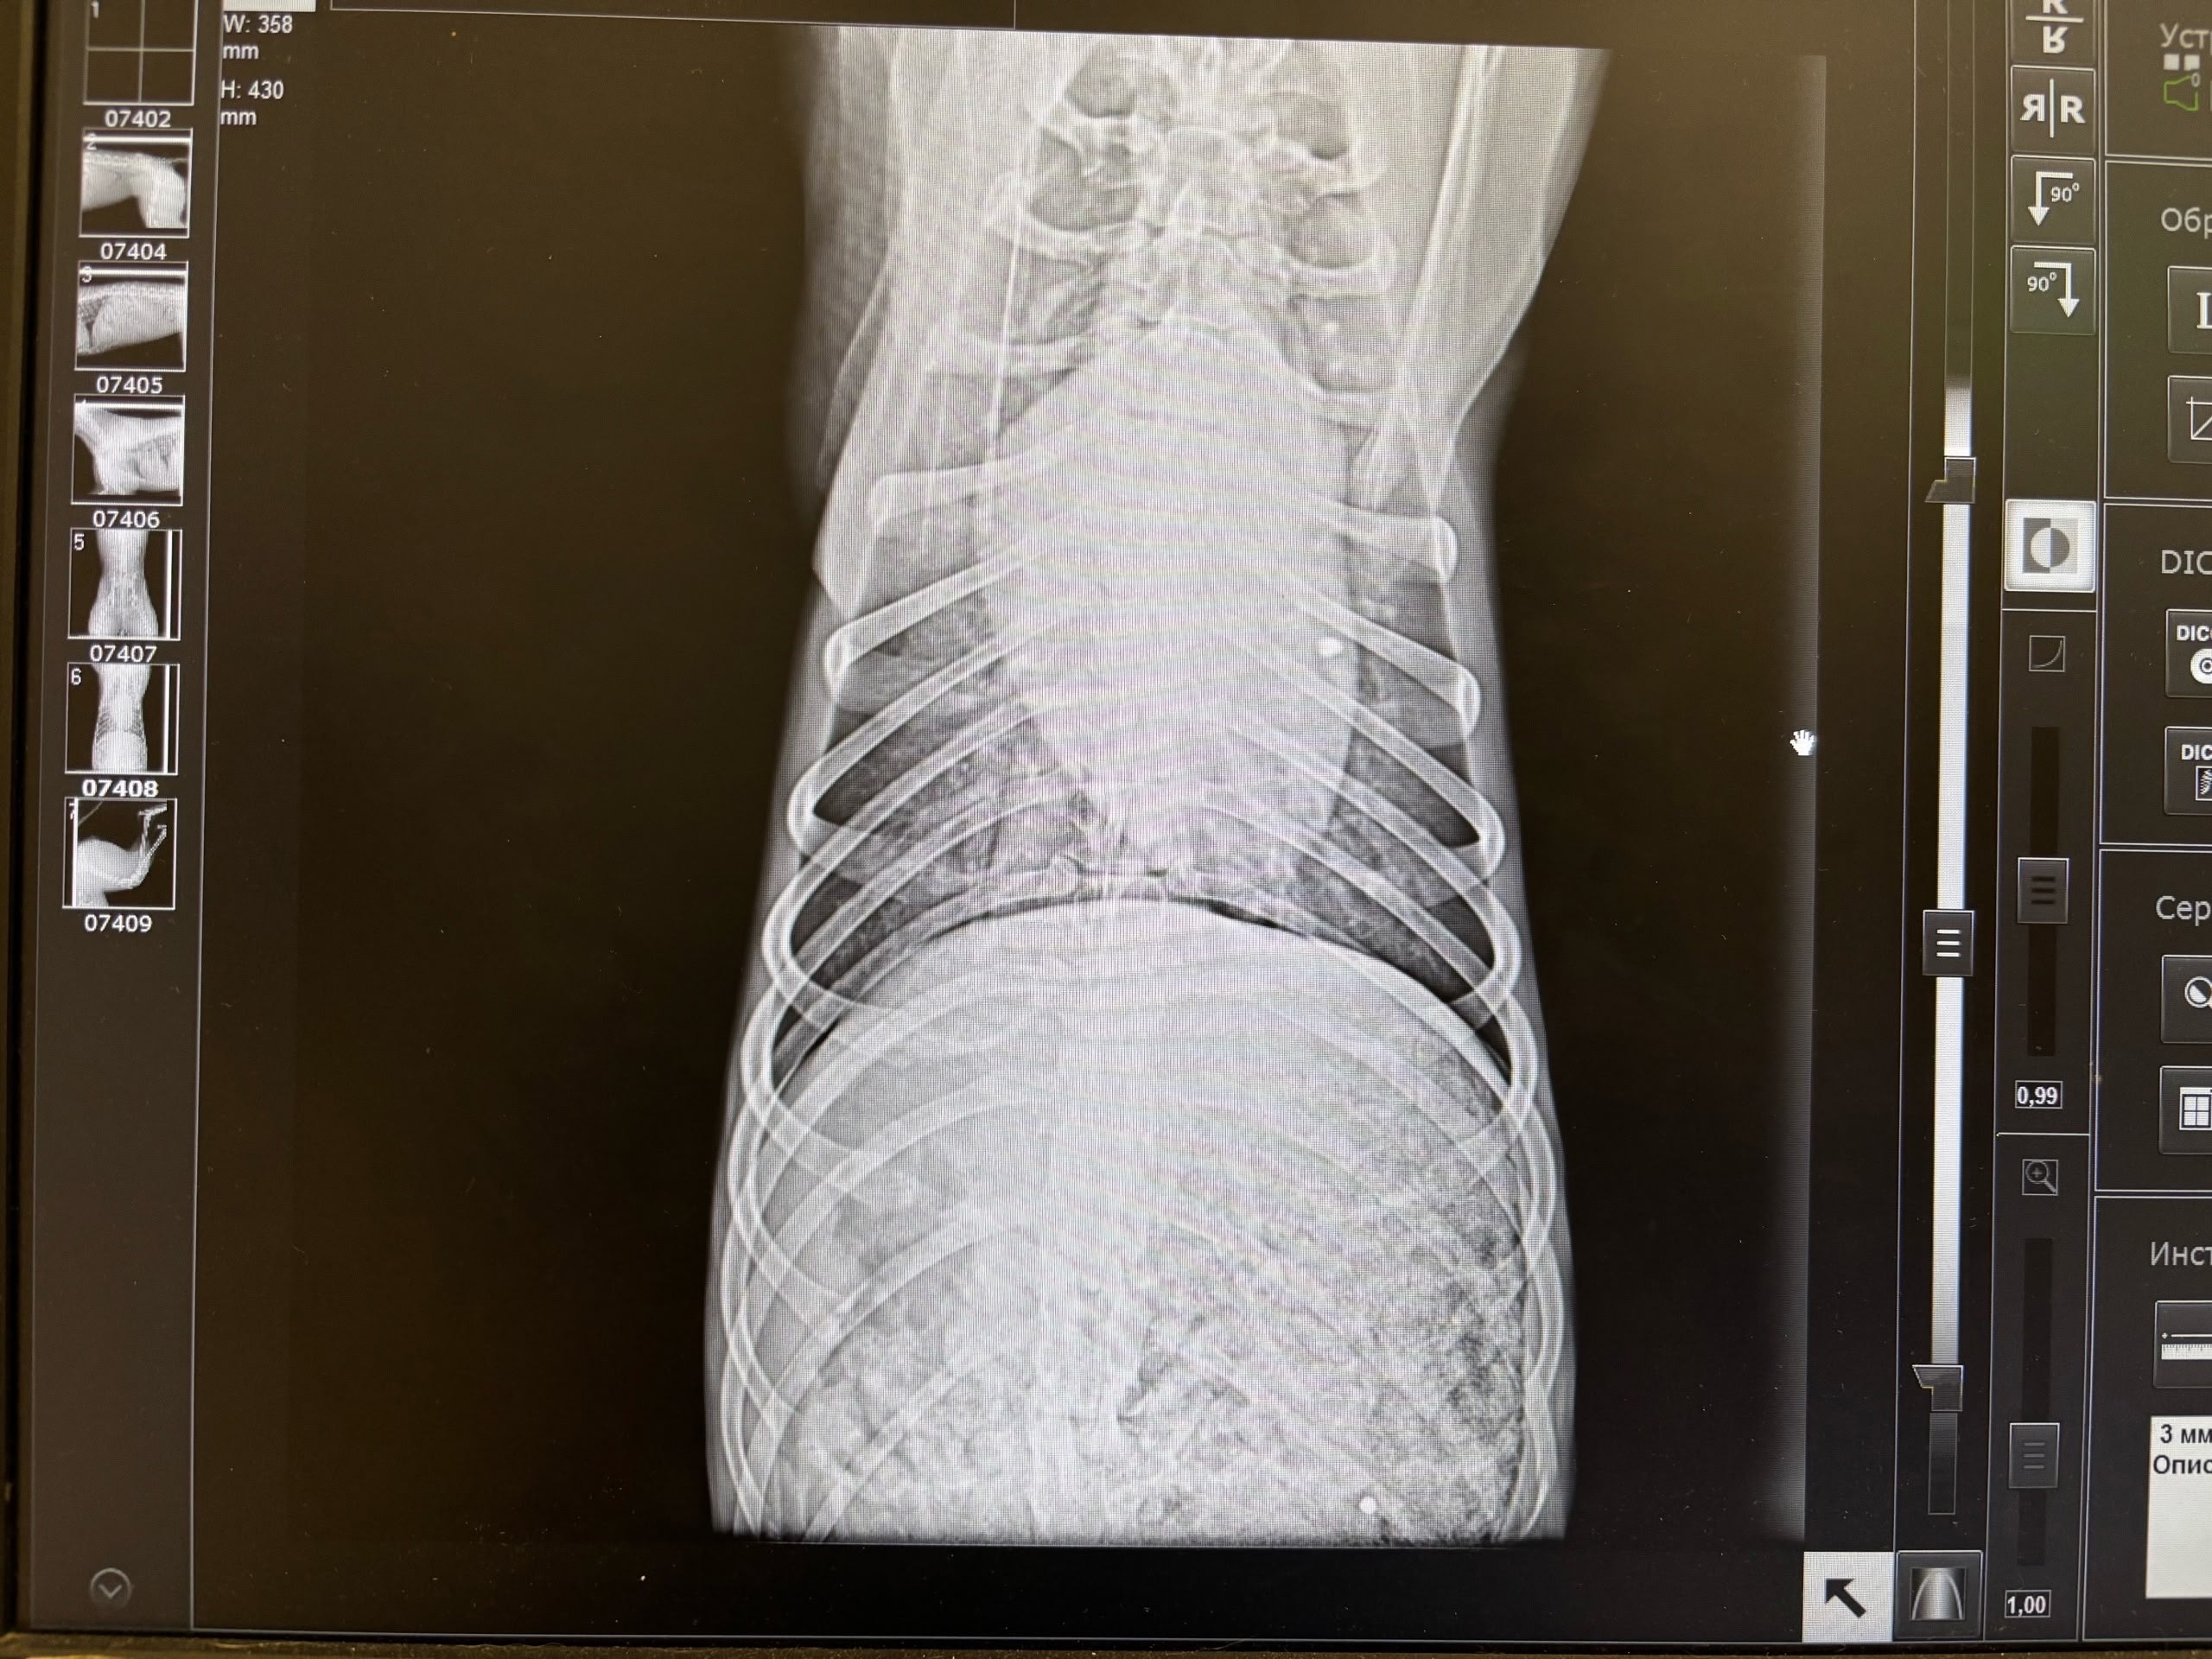

Мужчина по имени Вадим рассказал 78.ru, что отвел своих собак домой, а затем вернулся и при помощи шлейки кое-как вытащил пса, а затем передал волонтерам. Те отвезли его в выборгскую ветклинику, где рентген показал наличие дроби в позвоночнике и мягких тканях.

Позже Вадим нашел еще одну простреленную собаку, сучку, в поле и на этот раз сам отвез ее ветеринарам. И вновь на снимке медики увидели дробь.